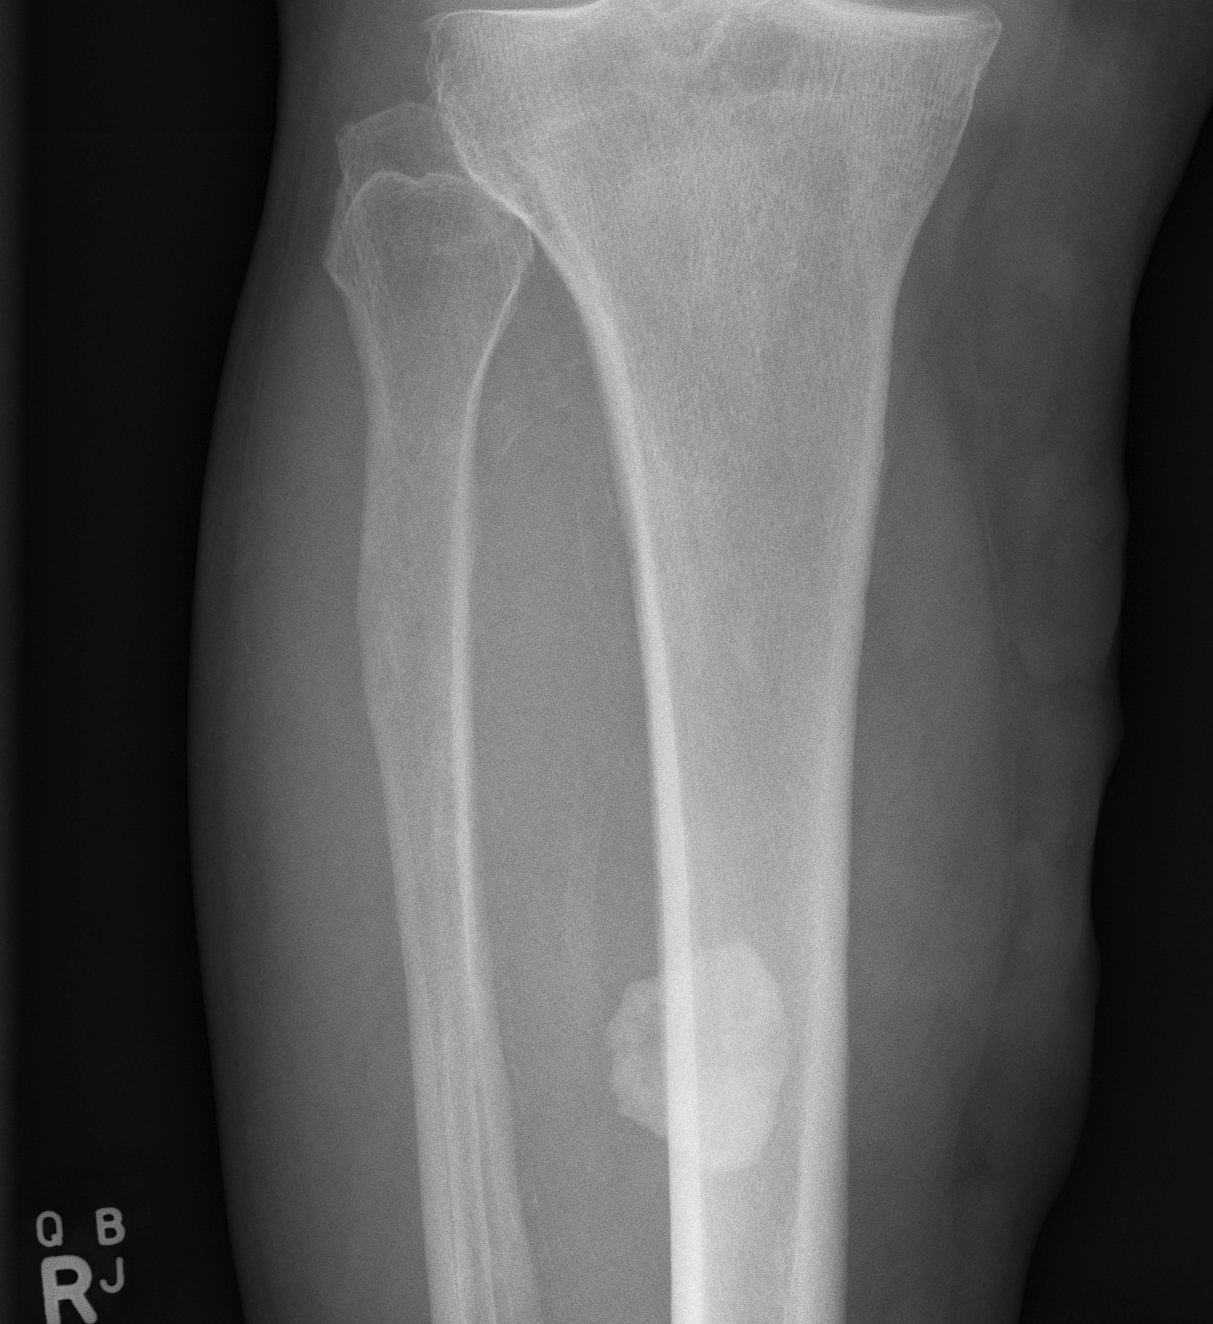

Direct blow to quadriceps / deltoid

X-ray

Changes occur 2-4 / 52 after injury

Initial cotton candy appearance

- then osseous in appearance

- not attached to bone

- can be resorbed

Mature bone peripherally